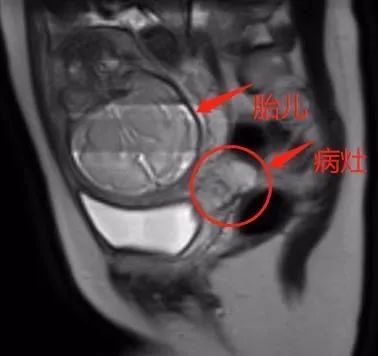

史文静带领团队查阅大量资料,了解国内外最近的诊治进展,多次组织妇产科与产科、儿科、麻醉科、放射科、外科、血液科等院内多学科团队人员充分讨论、反复研究,考虑如何有效治疗母体肿瘤的同时最大化保护胎儿安全,为小均制定个性化治疗方案,最后决定先做两个疗程的新辅助化疗,控制疾病进展,同时密切关注胎儿发育,尽量延长孕周再行剖宫产,并为小均施行宫颈癌根治手术。

国内外已有的实例表明,由于孕晚期胎儿大部分器官已发育完成,新辅助化疗的药物导致胎儿畸形或者发育异常的可能性较小,多学科团队的讨论结果给了小均极大的安慰。

在医护人员的帮助下,小均勇闯一道道难关,坚持配合治疗。“我要保住这个孩子。”幸运的是,每次接受新辅助化疗后,肿瘤均有所缩小,这更坚定了她的信心。